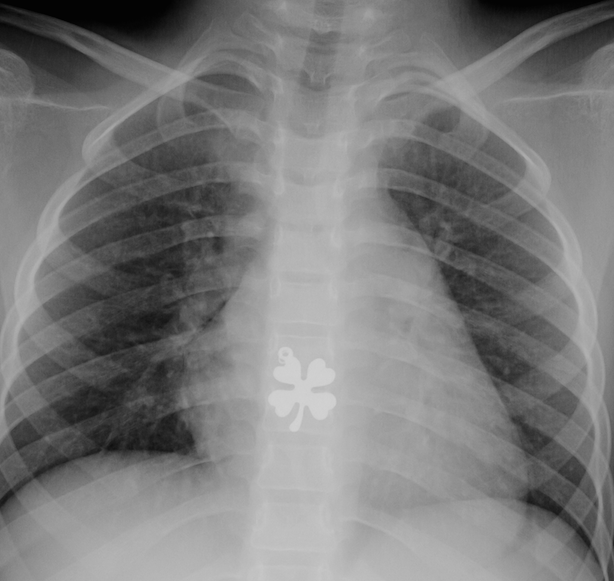

5. Coin ingestions/Blunt objects. Figure 6. “>250,000 ingestions and 20 deaths reported in the United States during a 10-year period.”

- For esophagus: If symptomatic, emergent removal; if asymptomatic, then urgent removal. Report recommends check X-ray immediately before sedation. While the report does not address this, a possible alternative to x-ray would be the use of a metal detector. “Consider glucagon if distal esophageal coin or if endoscopy not readily available.”

- For stomach: No endoscopy needed. Repeat X-ray at 2 weeks. Remove if not passed w/in 2-4 weeks. Report recommends check X-ray immediately before sedation. While the report does not address this, a possible alternative to x-ray would be the use of a metal detector.